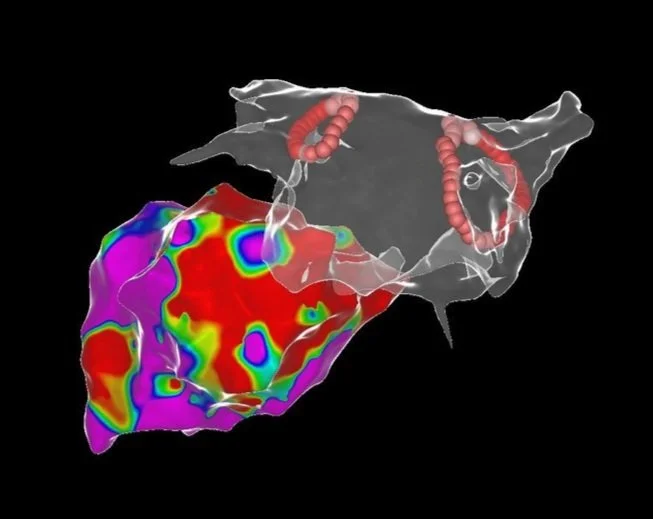

Links: Ultraschallbild eines Herzens, rechts: farbcodierte Substratkarte des Herzens